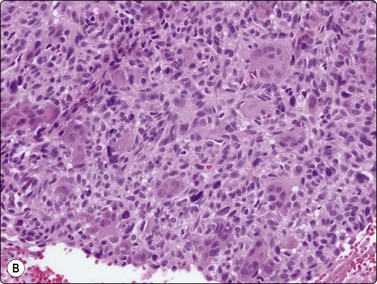

image image

Fig. 11.15 Osteoclastic adenocarcinoma (pancreas)

(A) Two osteoclastic type giant cells mixed with a poorly cohesive cluster of large, highly atypical epithelial cells (H&E, HP); (B) Cell block section corresponding to A (H&E, IP).

image

Fig. 11.16 Anaplastic pancreatic carcinoma

Highly pleomorphic mainly dispersed mononuclear and multinucleated tumor cells with macronucleoli (MGG, HP).

Other variants of pancreatic cancer

Pure osteoclastic giant cell tumors of the pancreas also require cytologic recognition as their behavior pattern may be more indolent than that of usual ductal carcinoma.99 Osteoclastic cells, with clustered bland nuclei disposed in dense cytoplasm, are interspersed with mononuclear cells displaying identical, uniform nuclei (Fig. 11.15).99,100 It is mandatory to distinguish this from another carcinoma variant, pleomorphic giant cell tumor (sometimes called anaplastic carcinoma) of the pancreas, which, as its name implies, also contains giant cells but with anisokaryotic daughter nuclei and macronucleoli (Fig. 11.16). Phagocytosis of inflammatory cells by tumor cells is common, and residual recognizable adenocarcinoma may be seen. This is the most lethal of all the pancreatic malignancies.101,102 Interestingly, mixed forms, containing both osteoclastic and pleomorphic giant cells, occur.103,104 Most reports indicate the prognosis to be extremely poor, approximating that of the pleomorphic variant.